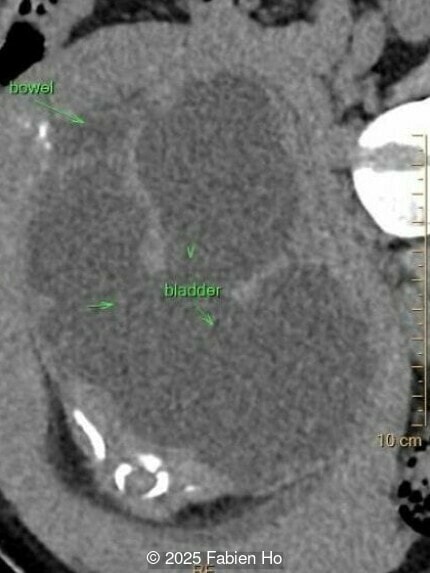

Axial image of the abdomen

Image 7 Axial image of the abdomen

Axial image of the fetal pelvis

Image 14 Axial image of the fetal pelvis

Our prenatal ultrasound revealed a male fetus with megabladder, dilation of both ureter and kidneys, and thinned kidney parenchyma consistent with Lower Urinary Tract Obstruction (LUTO).  Additional findings suspected on ultrasound and confirmed on computed tomography included:

At 36 weeks gestation, the abdominal findings were unchanged however, the bones appeared short (<1st percentile) and the spine had an unusual appearance, therefore a computed tomography was performed at 37 weeks gestation.